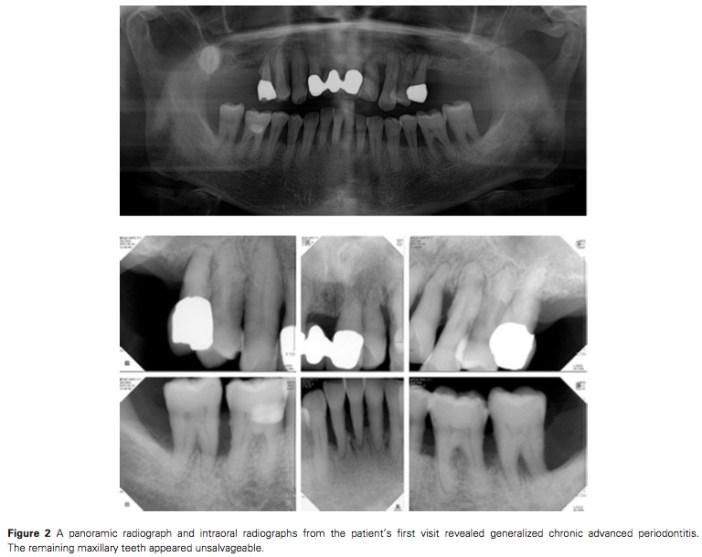

這個case report是一個49歲的女性患者, 因為全口牙周病以及後牙缺牙, 一開始看起來很糟糕的情況. 治療只拔除了左下7, 然後做了牙周的phase I and II的治療, 在上顎後牙各植了2顆ITI. 五年的追蹤下結果相當的理想. 我目前也有case是類似這樣的情形, 在後牙以植牙重建後牙咬合後, 前牙原本mobility III的牙齒竟然完全不搖了…但是我並沒有將剩下的牙齒splinting起來, 這我需要再評估看看. Splinting是雙面刃, 如果因為不好清潔而牙周更糟糕反而全盤皆輸.